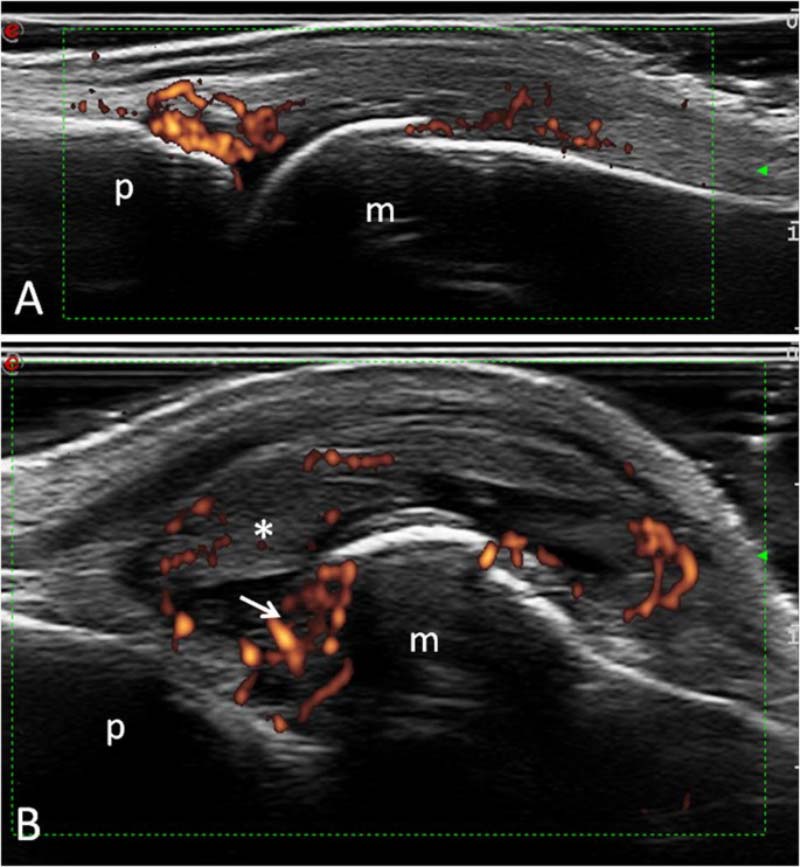

Siêu âm sử dụng sóng âm tần số cao để tạo ra hình ảnh các cơ quan và mô trong cơ thể. Bác sĩ sẽ bôi một lớp gel mỏng lên da, sau đó đặt đầu dò lên vùng cơ thể (tùy bộ phận bị ảnh hưởng). Đầu dò chuyển đổi dòng điện thành sóng âm tần số cao và truyền vào cơ thể. Sóng âm dội lại từ cấu trúc bên trong và trở lại đầu dò. Đầu dò chuyển sóng thành tín hiệu điện. Máy tính sẽ chuyển tín hiệu điện thành hình ảnh, video.

Sóng siêu âm có thể dùng để chẩn đoán các vấn đề về xương khớp: